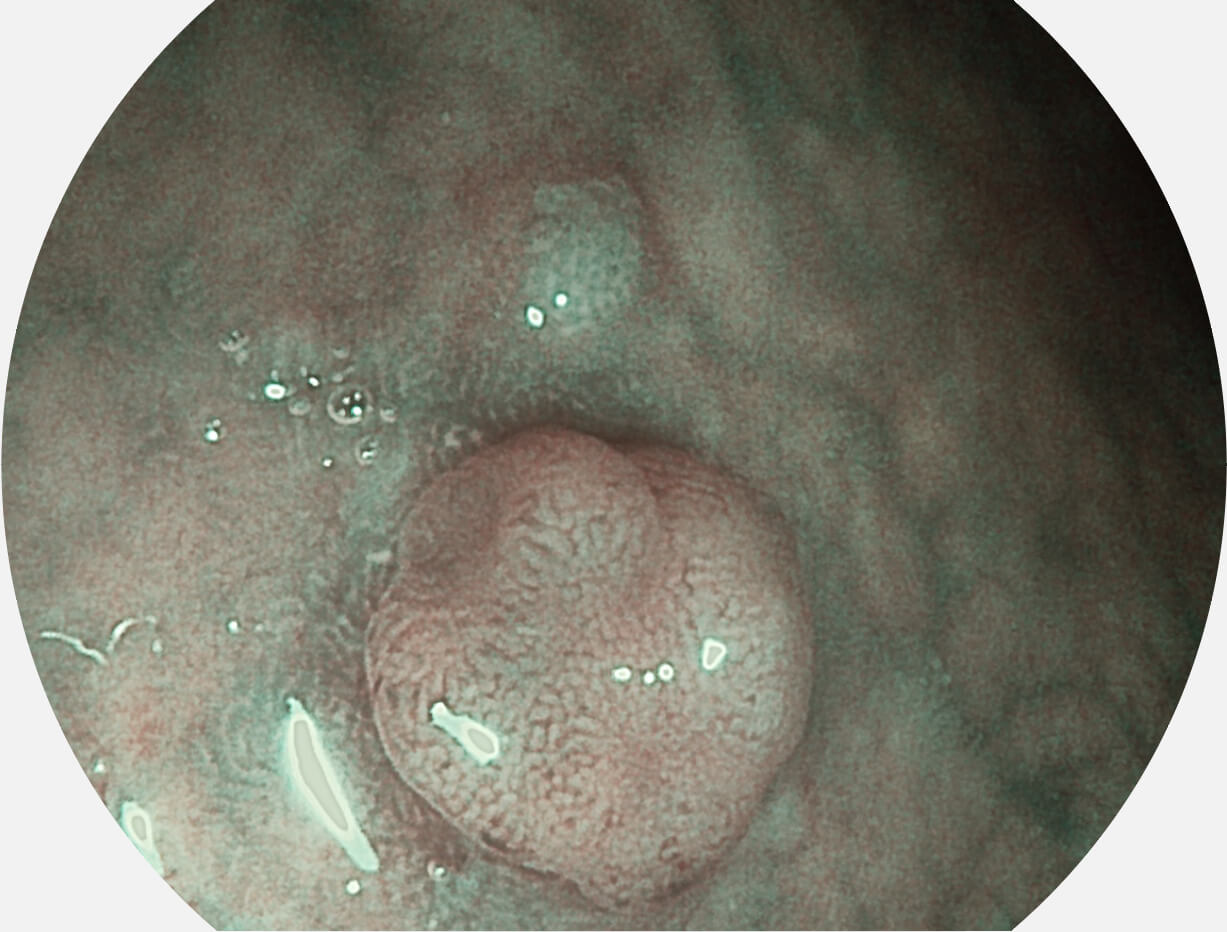

强调浅层黏膜结构的同时,保证照明亮度和提升浅层微血管与中层血管颜色对比度,病变边界更清晰。

• 白光图像 VIST图像